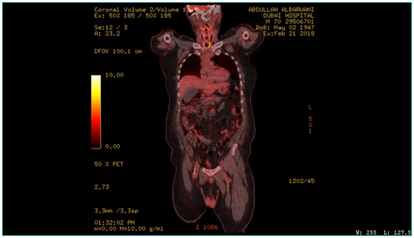

A biopsy was taken and histopathology was done using immunohistochemically markers and showed angiosarcoma, PET CT scan was performed on 21/02/2018 and showed the following: hypermetabolic suspicious lymph node in the right infraclavicular region, hypermetabolic focus in the region of the left mandible, adjusting left margin of the tongue and the hypopharynx (Figure 4–6). Patient was diagnosed before as squamous cell carcinoma of the right lateral side of the tongue.  Patient was operated in Oman on 8th November, 2006 for a white tongue lesion, and then operated again on 13th December, 2006 for tongue carcinoma. Lastly, partial Glossectomy was done for recurrent tongue carcinoma on 24th March, 2010 (Figure 7). After surgery, patient received total radiotherapy treatment of the face and neck using 6 MV photons, 2 fields and a total dose of 60Gy (44 Gy+20 Gy off cord) from 21st June, 2010 till 03rd August, 2010. Patient was then referred to a specialized center, where further management was done. This case was reported to high light an infrequent long-term complication of radiotherapy.

Figure 4 PET CT scan, showing hypermetabolic focus at the hypopharyx, post cricoid area.

Figure 5 PET CT scan, showing hypermetabolic focus at the region of left mandible, adjusting left margin of the tongue.

Figure 6 PET CT, showing hypermetabolic suspicious lymph node in the right infraclavicular region, hypermetabolic focus in the region of left mandible.